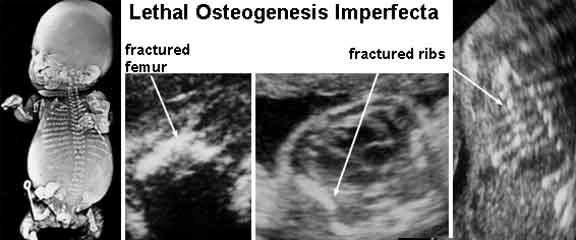

What is Osteogenesis Imperfecta Type II?

disorder of production, secretion or function of collagen

most severe form

Osteogenesis Imperfecta type 2

What is Osteogenesis Imperfecta Type II characterized by?

bone fragility caused by hypominerization

What can delivery trauma lead to with Osteogenesis Imperfecta Type II?

intracranial hemorrhage

stillbirth

What is Osteogenesis Imperfecta Type IV?

AKA Brittle bone

fractured or bowed

demineralization of bone

Whe does Osteogenesis Imperfecta Type IV occur?

can occur in 3rd trimester

usually does not present until after birth

What is the sonographic appearance of Osteogenesis Imperfecta Type IV?

decreased echogenicity

fractures

cortical bone thinning

excessive trabecular bone transparency